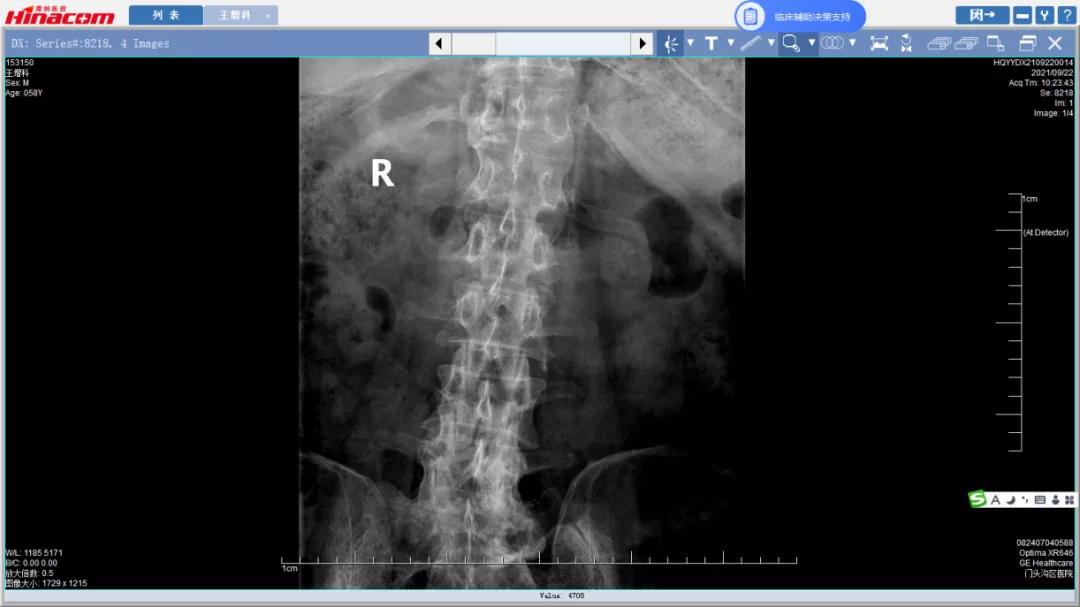

经匡正达主任诊治后,发现患者有先天性腰椎骶化,极易误诊,如果间隙做错了,那后果不堪设想。又考虑到患者要干农活,如果单纯椎管减压,有术后不稳的可能,而且患者长期生理性脊柱侧弯,综合考虑,最终决定为患者实施腰椎管减压的同时,进行椎间植骨融合钉棒内固定术。

腰34椎间盘--术前CT

腰45椎间盘--术前CT